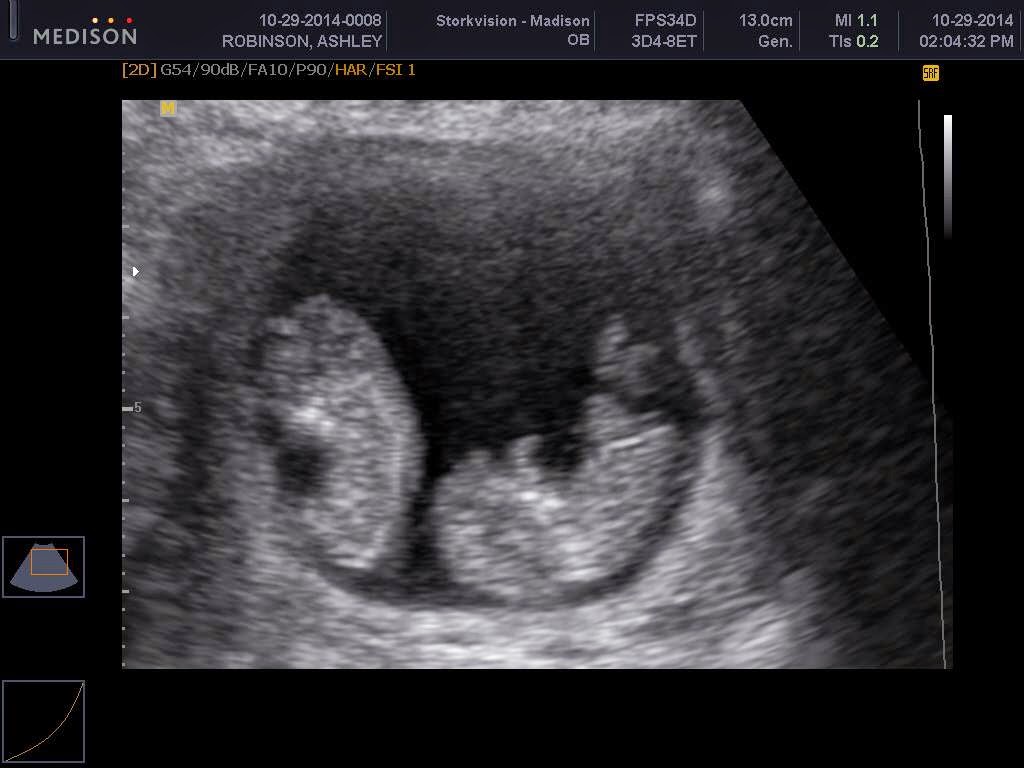

A blast from the past. The whole reason for this blog...my sweet homebirth baby Rosey Lei. Born August 13th, 2012